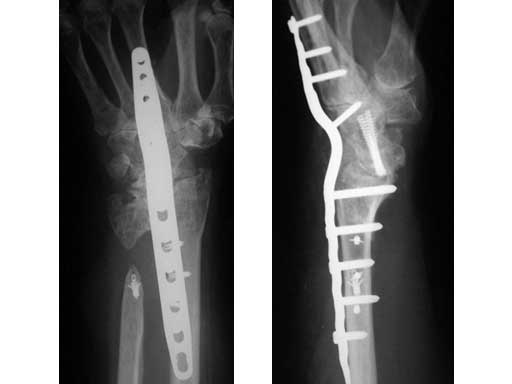

This case example is of a 73-year-old female now 13 years after a distal radius fracture and 2 years after a scapholunate-advanced collapse wrist procedure with Sauve Kapandji arthrodesis for combined posttraumatic instability of the carpus and posttraumatic arthritis of the DRUJ .

One year before her wrist fusion with LCP wrist fusion plate the patient underwent Achilles tendon allograft for stabilization of an unstable distal forearm articulation. The forearm was stabilized and her pain resolved only to return with radiocarpal crepitation and pain in the terminus of motion in flexion and extension. Her forearm was stable and her hand was warm and supple but she still suffered from rather severe osteopenia and arthrofibrosis of the small finger joints. Her dorsal wrist pain was of sufficient severity, frequency, quality, and location to justify trading her residual wrist motion for pain management. After diagnostic selective wrist joint injections her radiocarpal joint was determined to be a significant source of pain. She underwent successful radiocarpal arthrodesis with local bone graft.

Fig 1 Eight weeks after radiocarpal fusion. (left)

Fig 2 One year after distal radius ulnar joint interpostion arthroplasty. (right)